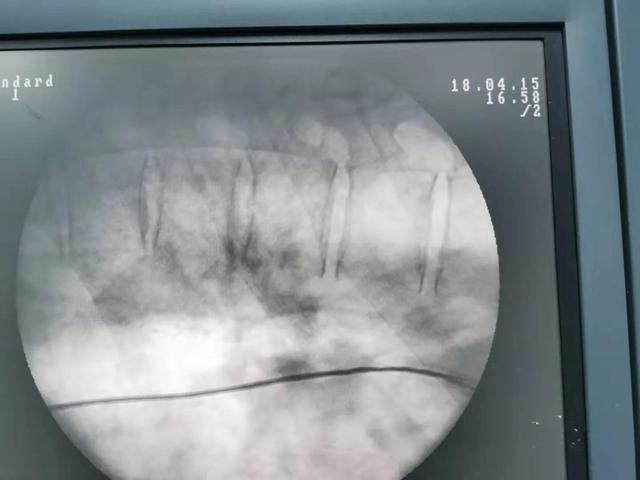

高周波熱凝固療法は、直径0.7mmの高周波針を使用し、C-armまたはCTガイダンスの下で穿刺し、病変椎間板に正確に到達して熱凝固のスイッチを入れる。熱放射に頼って髄核ヘルニアを小さくし、神経根の圧迫を和らげる。プラズマ手術と高周波熱凝固療法の違いは、ヘルニア髄核組織を直接蒸発させることです。

椎間板ヘルニアが大きい場合、椎間孔径手術の効果が良い。 椎間孔径手術の切開は小さく、通常7mm程度で、傍椎骨筋や靭帯を破壊せず、出血が少なく、脊椎の安定性に影響がなく、術後は神経圧迫が除去されるため、痛みの症状が早く緩和される。開腹手術は腰椎椎間板ヘルニアに腰椎変性症、骨棘、脊柱管狭窄症、神経根管狭窄症、靭帯石灰化などを伴う患者や、明らかに腰椎が不安定な患者が対象です。